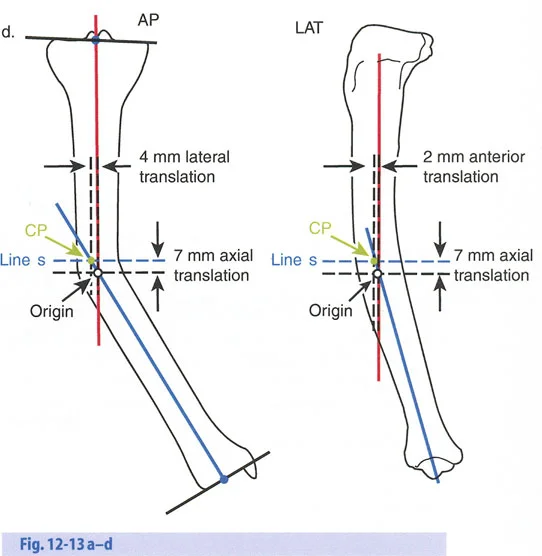

هذا الدليل الشامل يستعرض الاعتبارات الحاسمة لتطبيق الأجهزة، وتحديد مواضع المفاصل الاصطناعية (المفصلات)، وآليات الشد، والتسلسل الاستراتيجي للتصحيحات التدريجية. سواء كان الجراح يستخدم مثبتات إليزاروف الدائرية التقليدية، أو أنظمة الهيكسابود الحديثة (مثل جهاز تايلور الفراغي Taylor Spatial Frame)، أو المثبتات أحادية الجانب، فإن القواعد الهندسية التي تحكم مركز دوران الانحراف (CORA)، ومحور تصحيح الانحراف (ACA)، وانحراف المحور الميكانيكي (MAD) تظل مطلقة ولا تقبل الخطأ.

قواعد بالي لقطع العظم (Osteotomy Rules) في وضع الأجهزة

فهم قواعد بالي لقطع العظم أمر لا غنى عنه لتخطيط الإطار:

- قاعدة قطع العظم 1: عندما يمر قطع العظم ومحور تصحيح الانحراف (ACA) كلاهما عبر مركز دوران الانحراف (CORA)، فإن نهايات العظم ستنحرف دون ترجمة (انزياح). يتم استعادة المحور الميكانيكي، وتظل نهايات العظم متقاربة تمامًا، مما يخلق تصحيحًا كلاسيكيًا "إسفينيًا مفتوحًا" أو "إسفينيًا مغلقًا".

- قاعدة قطع العظم 2: عندما يمر محور تصحيح الانحراف (ACA) عبر مركز دوران الانحراف (CORA)، ولكن يتم إجراء قطع العظم على مستوى مختلف (غالبًا بسبب ضعف جودة العظم عند CORA أو مشاكل في الجلد)، فإن نهايات العظم ستنحرف وتخضع لترجمة محسوبة ومقصودة لإعادة محاذاة المحور الميكانيكي.

- قاعدة قطع العظم 3: (للاكمال) عندما يمر قطع العظم عبر مركز دوران الانحراف (CORA)، ولكن يتم وضع محور تصحيح الانحراف (ACA) خارج CORA، سيتم إنشاء تشوه ترجمة جديد، وهو خطأ شائع في وضع المفصلات غير المخطط له جيدًا.

في المنشآت القريبة من المفصل، غالبًا ما نعتمد على قاعدة قطع العظم 2. نظرًا لأنه لا يمكننا قطع العظم بأمان عند خط المفصل تمامًا (مركز دوران الانحراف CORA)، فإننا نقطع العظم في مستوى أدنى في منطقة الميتافيسيس. بعد تحقيق التصحيح الزاوي عبر المفصلات (محور تصحيح الانحراف ACA)، يتم إعادة محاذاة خطوط المحور الميكانيكي بشكل مثالي، ولكن نهايات العظم في موقع قطع العظم تتحرك بالنسبة لبعضها البعض.

حساب معدل الشد الحقيقي

لحساب المعدل الصحيح للشد عند المفصلة، نستخدم قاعدة المثلثات المتشابهة، والتي تعتمد أساسًا على القاعدة الهندسية للدوائر متحدة